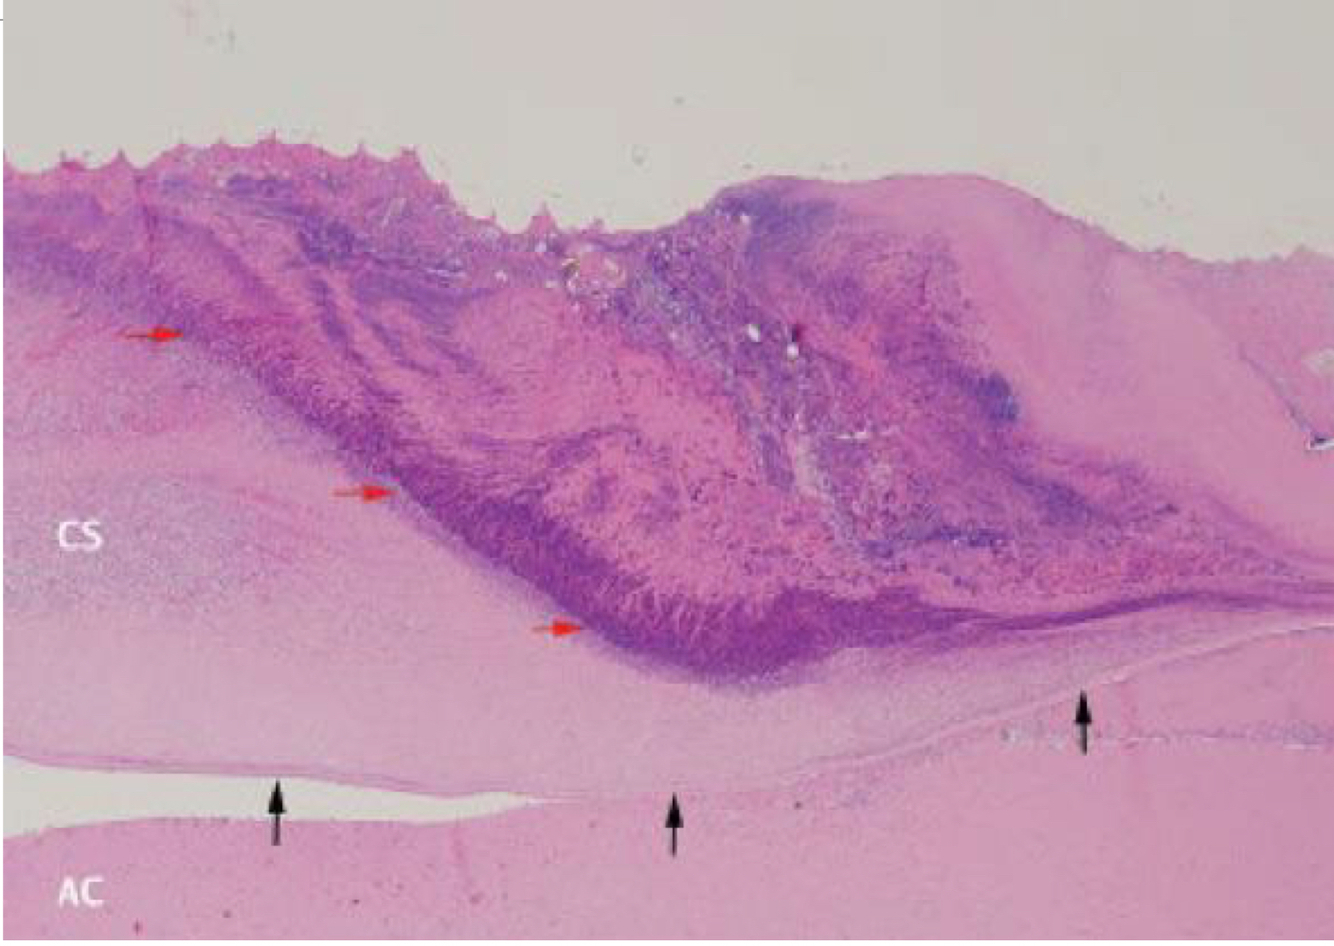

What a staphyloma? What is it commonly lined by? What is thought to be the cause?

circumscribed outpouching of the sclera due to weakening or thinning uveal tissue ---> pigmentation from choroid makes it look like a melanocytic tumor increased intraocular pressure from glaucoma, trauma, or scleritis

42

Staphyloma:

outpouching, can include cornea